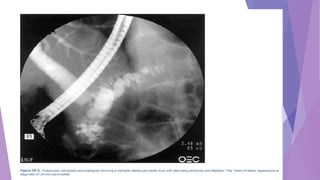

Endoscopic retrograde cholangiopancreatography (ERCP)

A characteristic "chain of

lakes" appearance of the

main pancreatic duct can

be noted on ERCP in

patients with severe

chronic pancreatitis.

The main pancreatic duct

is enlarged (greater than

1.5 times) with increased

tortuosity.

There is severe clubbing

and dilation of the side

branches.

Stone formation and

occlusion of the

pancreatic duct may

occur in this stage of the

disease

ERCP